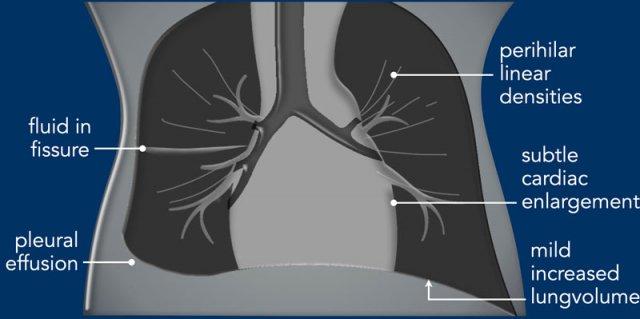

Imaging

- Mild increased lung volume.

- Interstitial edema resulting in perihilar linear densities.

- Subtle enlargement of the cardiac silhouette.

- Pleural effusions and fluid in the fissures.

- The radiological findings may be asymmetrical.